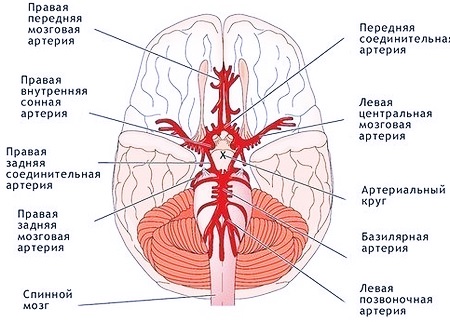

Анатомия: Задняя соединительная артерия мозга